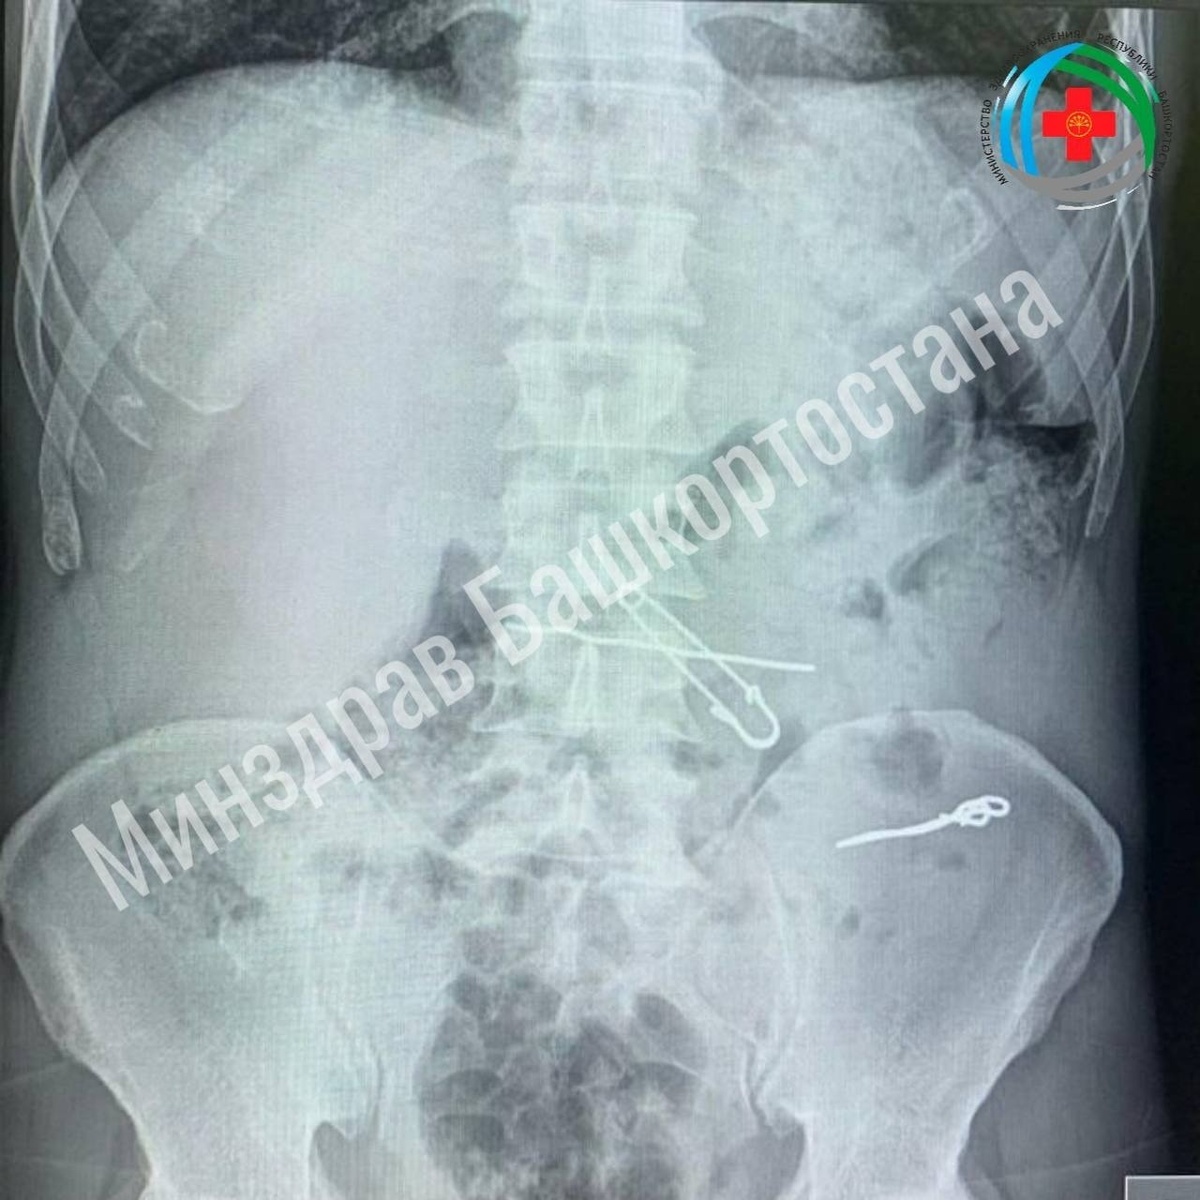

Уфимец проглотил ключи, скрепки, булавку и проволоку

Как сообщил в своих соцсетях министр здравоохранения РБ Айрат Рахматуллин, пациент обратился в приемный покой медучреждения с жалобами на боли в животе. По результатам обследований в толстой кишке у него обнаружили проволоки, скрепки длиной 47, 62 и 90 мм. В желудке же находились булавка и проволока. Мужчину госпитализировали в отделение гнойной хирургии для оперативного лечения.

Хирурги провели операцию и удалили инородные тела. Во время хирургического вмешательства была проведена контрольная рентгенография.